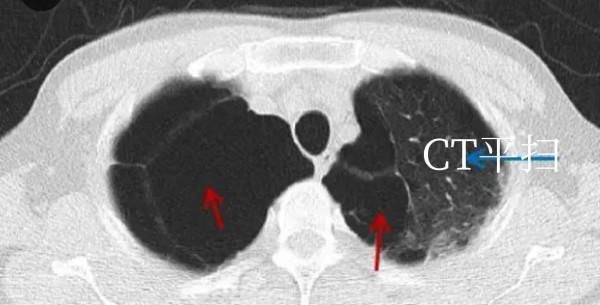

肺大泡常見於青年(先天性發育異常)和老年人(繼發性肺部病變)中, 少年因氣胸發作時 CT 發現肺大泡。老年人(吸菸者 主)及部分粉塵從業人員因體檢發現。肺大泡嚴重者大多有呼吸困難等症狀。胸腔鏡微創手術,是最佳選擇。薄層 CT 能夠很好區別肺大泡和氣胸。#創作#